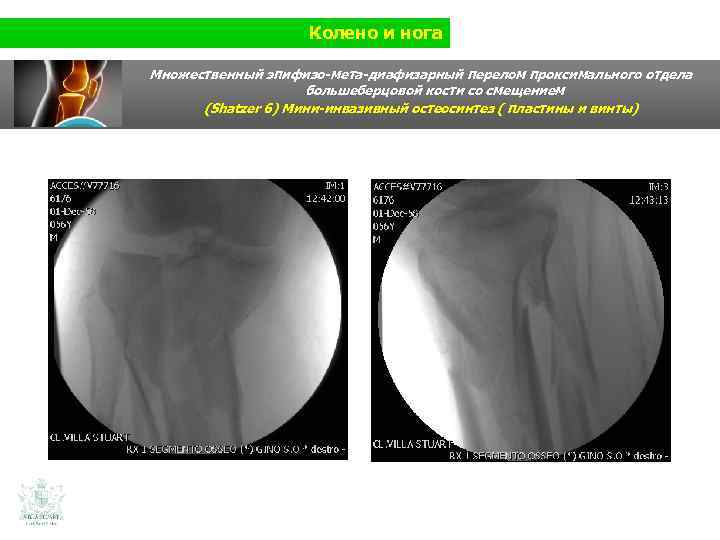

Колено и нога Клинический случай (колено и нога) Мужчина 56 лет Травма нижней конечности на мотоцикле Использования изображения в 3 D

Колено и нога Множественный эпифизо-мета-диафизарный перелом проксимального отдела большеберцовой кости со смещением

Колено и нога Множественный эпифизо-мета-диафизарный перелом проксимального отдела большеберцовой кости со смещением (Shatzer 6) Мини-инвазивный остеосинтез ( пластины и винты)